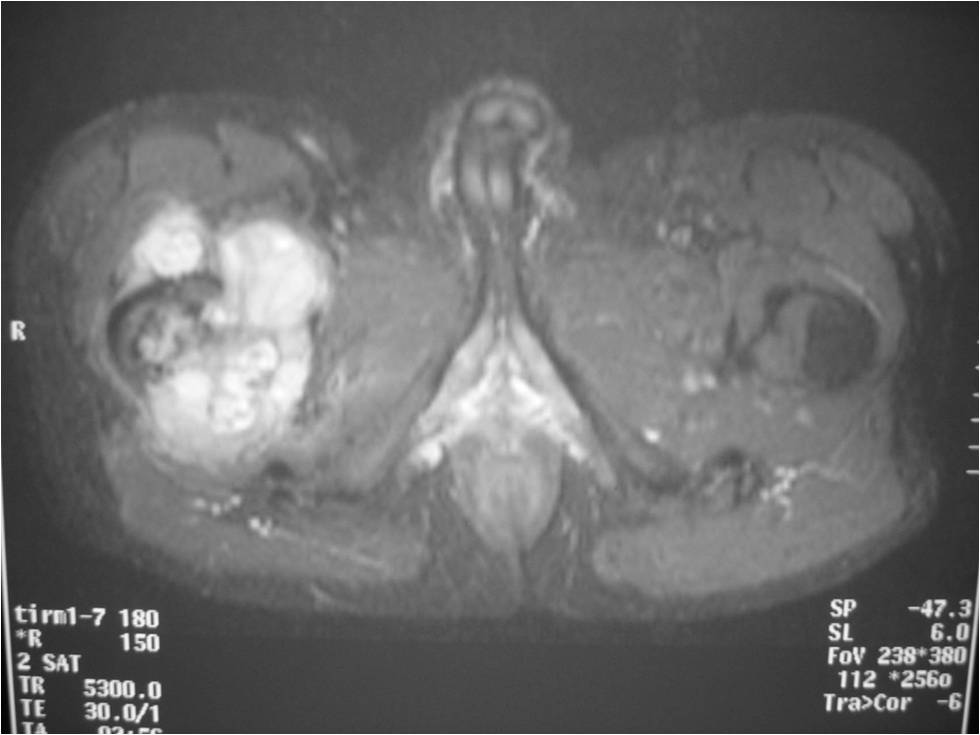

Radiographic Presentation

Radiology emulates pathology: Biphasic Tumor

- One region low grade chondrosarcoma

- Second more aggressive area with bone destruction, lysis of calcification, soft tissue mass

- Cortical permeation and a soft tissue mass in 70% of cases

Ill-defined, lytic intraosseous lesion

- Or extraosseous soft tissue mass

- Devoid of calcifications in continuity with lesions having the features of a cartilaginous tumor

Characteristically abrupt transition between chondroid tumor and dedifferentiated, lytic component

Bone may be expanded and adjacent cortex thickened

(Right Arrow)Aggressive Lytic Area (Dedifferentiated Sarcomatous Component) Cortical Destruction Soft Tissue Mass without Calcification